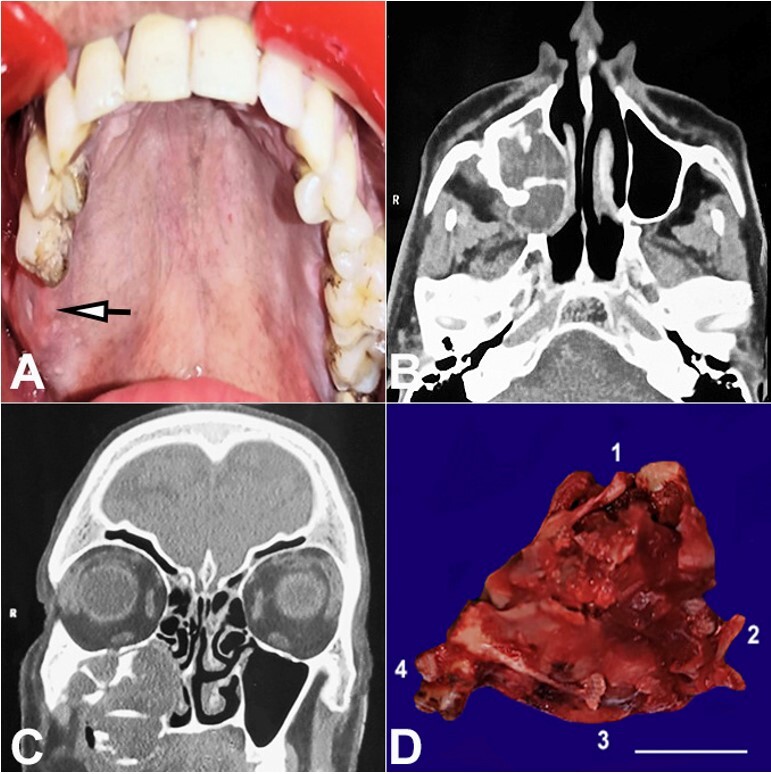

Dentinogenic ghost cell tumor (DGCT) is a rare benign neoplasm form of calcifying odontogenic cyst (COC) characterized by ghost cells. Although benign, it presents an aggressive behavior. DGCT accounts for 2% to 14% of all COCs and less than 0.5% of all odontogenic tumors. It is a benign odontogenic tumor despite its local invasion and the likelihood of recurrence. To detect recurrence, central DGCT patients must be monitored long-term. We present the case of a 51-year-old male who reported pain in the right upper back tooth region. On examination, a soft to firm, bright red swelling was present in the buccal vestibule and gingival margin of the maxillary right first and second molar, which extended up to the palate. Histopathological analysis confirmed the diagnosis of a DGCT, which occurred in a previously treated calcifying odontogenic cyst. The case is reported here, along with a review of the literature update of such recurred instances in the past.